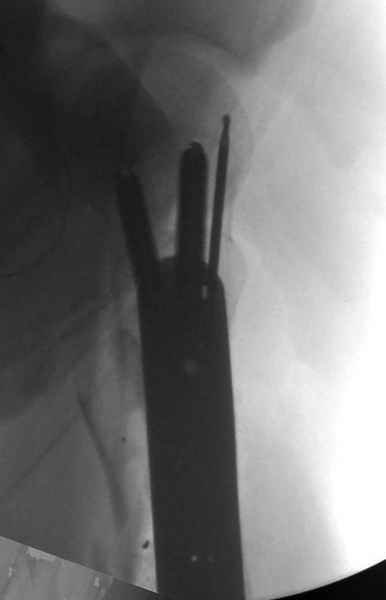

Перелом низкоскоростным оружием, типа пистолетного, так что не стали гоняться за пулевыми фрагментами. С нервом пока подождем, иногда нерв восстанавливается если не прямое попадание в нерв, а "сотрясение" (shock wave injury).

Из всех типов фиксации взяли малоинвазивную технику мостовидной пластиной, использовали Locking проксимальную Synthes пластину.